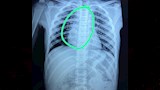

تمكن فريق طبي بمستشفى بنها التخصصي للأطفال، من إنقاذ حياة طفل يبلغ من العمر 10 سنوات، بعد أن ابتلع لمبة ريموت، مما تسبب في عدم استطاعته التنفس وسد مجرى الهواء، حيث جرى التدخل الجراحي السريع واستخراج الجسم الغريب وتماثل المريض للشفاء.

كشف بيان من مستشفى بنها التخصصي للأطفال أن المستشفى استقبل طفل 10 سنوات يعاني من عدم القدرة على التنفس، حيث أكد ولي أمر الطفل أنه تنقل بين العديد من مستشفيات القاهرة لإنقاذ طفله، فتوجه إلى مستشفى الأطفال التخصصي ببنها، حيث ابتلع الطفل لمبة ريموت كنترول استقرت بالقصبة الهوائية.

أوضح الدكتور محمود البرنس عباس، مدير عام المستشفى، أنه على الفور جرى عمل الإشاعات اللازمة وتجهيز الحالة ودخولها إلى غرفة العمليات وجرى استخراج اللمبة بواسطة منظار القصبة الهوائية.